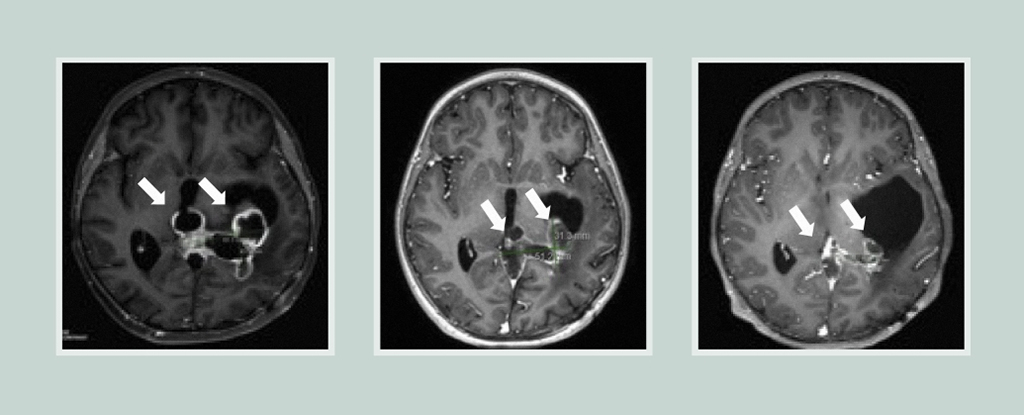

Researchers have developed a noninvasive nasal nanotherapy using gold-based spherical nucleic acids that successfully eradicated glioblastoma tumors in mice by activating immune pathways, offering a promising new approach for treating deadly brain cancers.